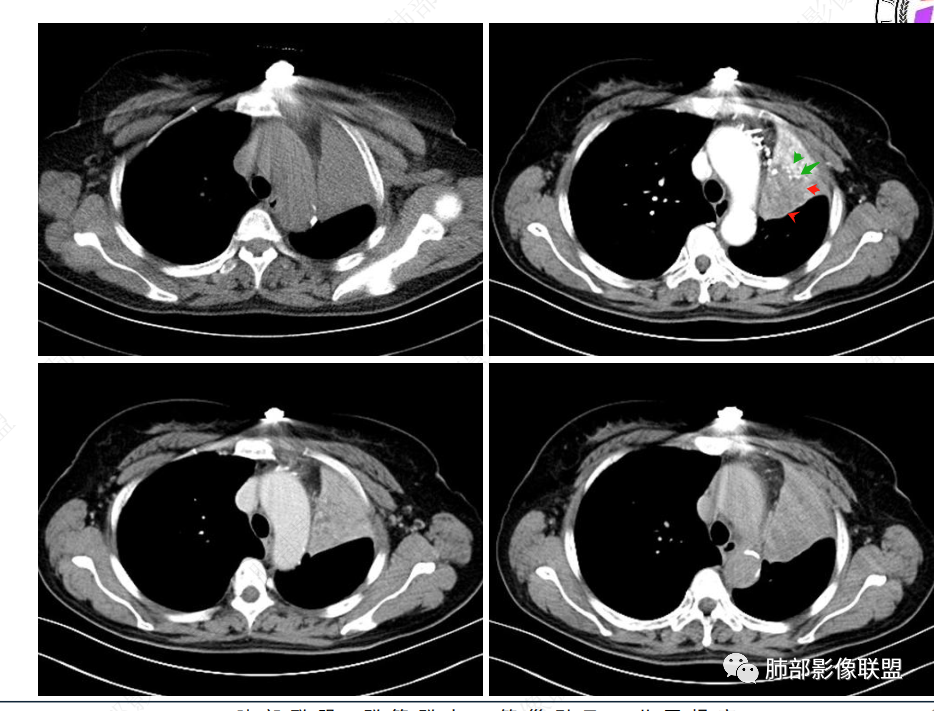

2、影像表现:正常肺背景,左肺上叶支气管腔内占位,上叶支气管截断,远端肺组织不张,强化差异衬托出肺门区结节影或块状影。增强扫描腔内占位轻中度不均匀强化,可见坏死,远端粘液栓,局部肺动脉受压、侵犯,纵膈淋巴结无明显肿大,无胸腔积液。

3、综合分析:老年女性,支气管腔内占位明确,病灶向周围侵犯,诊断恶性肿瘤并肺不张问题不大。需要考虑到的疾病谱有鳞癌、腺样囊性癌、粘液表皮样癌、类癌、小细胞肺癌等。

就本例而言,患者为女性,无肺气肿背景,未提及吸烟史,影像上强化程度偏轻,未见湖泊样坏死,尽管中央型肺癌中以鳞癌最多见,且造成完全阻塞及肺不张,但在女性患者诊断鳞癌仍需谨慎。支气管腔内结节,强化程度轻,涎腺肿瘤需要考虑,不典型类癌也不能除外。女性患者,未提及吸烟史,尽管未见纵膈淋巴结明显肿大,但支气管明显相关,小细胞肺癌亦应当重点排除。